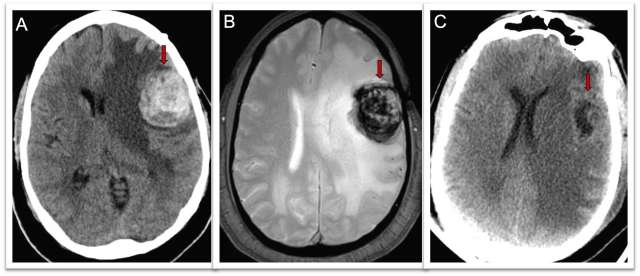

Treatment of a CCM depends on its location and the symptoms it causes (most commonly from bleeding events). Your doctor may recommend monitoring it with MRIs and treating symptoms with medications (Figure 2). If surgical treatment is necessary, the cerebrovascular surgeons at UCLA are expertly trained in this specialized procedure, and have performed a high volume of these surgeries. In each case, we aim to perform these surgeries in the most minimally-invasive way possible, removing the CCM with the least disruption of normal tissue.

Brain CT scan

Figure 2. Cerebral Cavernous Malformation Treatment - Brain CT scan in a patient having difficulty speaking shows a 3cm mass containing blood (red arrow). Figure 2b: Brain MRI showing the mass with blood inside (red arrow). Figure 2c: CT scan of the brain